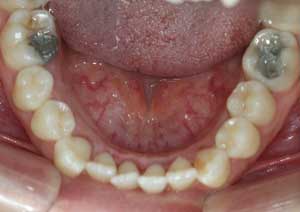

En orthodontie, une béance antérieure est une malocclusion caractérisée par l’absence de contact entre les incisives supérieures et inférieures lorsqu’on ferme les dents.

Traitement : Une ingression des molaires maxillaires avec une égression contrôlée du secteur antérieur a été réalisée à l’aide des arcs dits “Rocking Chair”, associés à des élastiques antérieurs portés de canine à canine, à droite et à gauche.

Cette mécanique permet de corriger la béance antérieure tout en conservant un contrôle précis de la position des dents antérieures et postérieures.

Avant